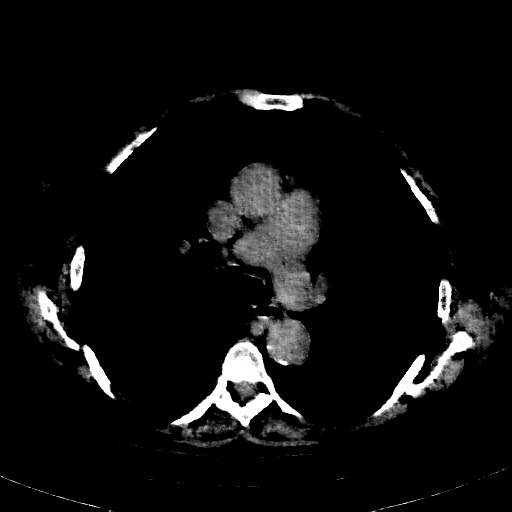

Reconstructed NATIVE CT scan (cycle consistency)

Full window (WL 1023.5, WW 4095 β†’ Low βˆ’1024, High +3071)

Actual HU range: [-1024.0, 609.2]